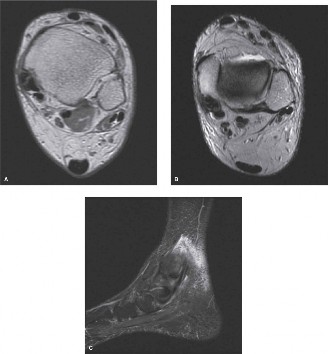

- Magnetic Resonance Imaging: MRI is the gold standard for evaluating tendon integrity. Axial and sagittal T2-weighted fluid-sensitive sequences are optimal for identifying tenosynovitis (circumferential fluid within the tendon sheath), tendinosis (intrasubstance signal alteration and tendon thickening), and longitudinal split tears.